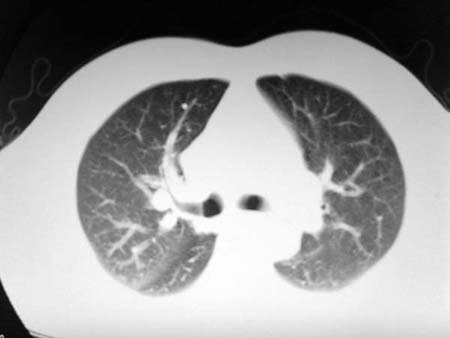

以下是引用qian在2008-4-27 17:02:00的发言:[br]考虑右下肺肺段隔离症伴有感染,建议做增强看看。

以下是引用zsl6918在2008-4-27 17:13:00的发言:[br]考虑右肺下叶炎性病变可能性大,建议抗炎治疗后复查,现有资料不能完全除外肺癌可能。